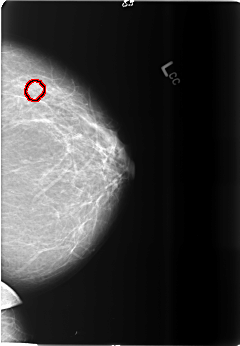

B_3494_1.LEFT_CC

LEFT_CC LINES 5880 PIXELS_PER_LINE 4064 BITS_PER_PIXEL 12 RESOLUTION 50 OVERLAY

FILE: B_3494_1.LEFT_CC.OVERLAY

TOTAL_ABNORMALITIES 1

ABNORMALITY 1

LESION_TYPE CALCIFICATION TYPE ROUND_AND_REGULAR-AMORPHOUS DISTRIBUTION N/A

ASSESSMENT 4

SUBTLETY 3

PATHOLOGY BENIGN

TOTAL_OUTLINES 1

BOUNDARY